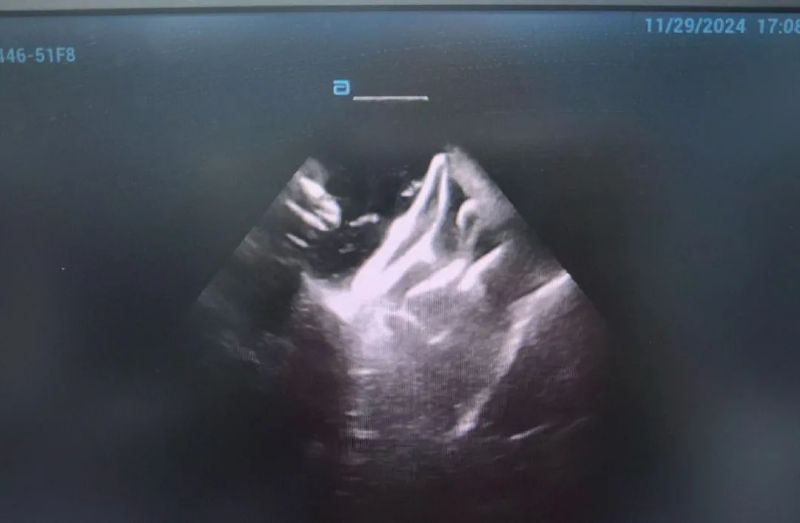

此次手术患者均为持续性房颤患者,由延安大学咸阳医院吴栋梁院长、心律失常专家刘雄涛副院长带领介入团队开展,安全高效、圆满完成手术,手术过程患者全程清醒,术中自诉感觉良好,无痛苦感受。术后患者的心律恢复并维持了窦律,目前恢复情况良好,无任何并发症出现。